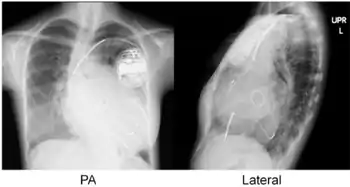

Cardiac resynchronisation therapy (CRT or CRT-P) is the insertion of electrodes in the left and right ventricles of the heart, as well as on occasion the right atrium, to treat heart failure by coordinating the function of the left and right ventricles via a pacemaker, a small device inserted into the anterior chest wall.[1]